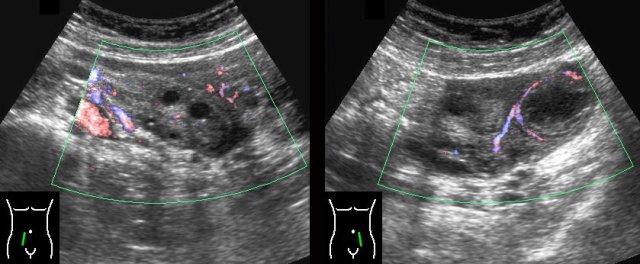

Ca lâm sàng 3

Các hình ảnh này của một phụ nữ 17 tuổi với cơn đau hố chậu phải cấp tính, dữ dội. CRP bằng 1.

Siêu âm phát hiện một nang buồng trứng phải thành dày, bờ không rõ và dịch tự do (*) trong túi cùng Douglas.

TVUS xác nhận hình ảnh dịch và một nang xẹp một phần, dễ ép xẹp ở buồng trứng phải.

Buồng trứng trái bình thường (hình dưới bên phải).

Cơn đau giảm dần và các xét nghiệm duy trì trong giới hạn bình thường.

Trong vòng một tuần, hình ảnh siêu âm hoàn toàn trở về bình thường.

Chẩn đoán có khả năng nhất: nang chức năng vỡ.